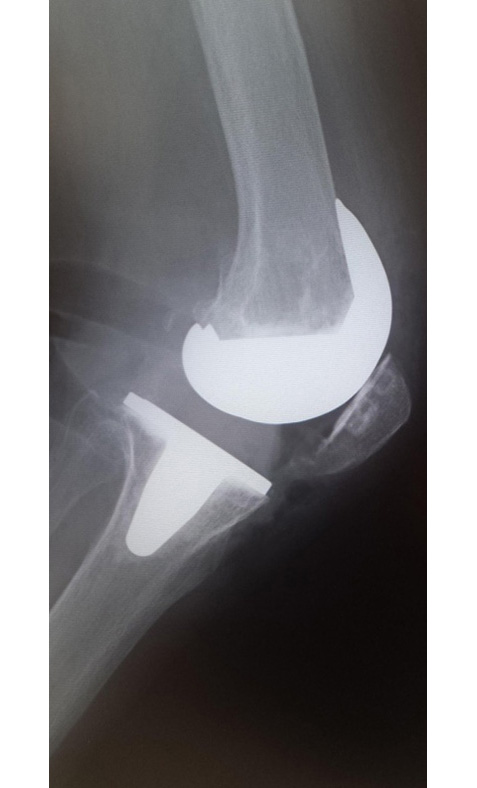

当院でおこなった人工膝関節全置換術(TKA)

側面像